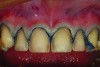

Fig 3. This oblique view of the preoperative smile shows the extreme size difference between the large maxillary anterior teeth and the smaller, diminutive posterior teeth—the “posterior gummy smile.”

Figure 3

Figure 1 and Figure 2 show full-smile and intraoral full-arch views of the patient’s preoperative condition. The retracted full-smile image revealed disparate gingival heights over teeth Nos. 8 and 9. The proximal-facial line angles, particularly of the maxillary central incisors, were indistinct and rounded, contributing to a more “square” silhouette of the facial outline form. The maxillary anterior teeth appeared much larger in the cervico-incisal dimension with a dramatic decrease in height starting in the first premolar area (Figure 3). Esthetic harmony cannot always be achieved without addressing both hard and soft tissues and unfortunately, some clinicians “only see the white and not the pink.” The decreased height of the posterior teeth helped to contribute to the problem of the anterior teeth appearing too large. Prior to tooth preparation, a soft tissue correction was made with a diode laser (Picasso Diode Laser, AMD Lasers, amdlasers.com), which made the bulbous emergence profile of the existing veneer painfully evident. Because the patient had no second premolar due to extraction and orthodontics performed when the patient was younger, symmetry of the positions of the gingival margins was very important to the overall esthetics of the case. An imaginary line was drawn from the cervical height of contour of the maxillary cuspid to the gingival margin above the mesio-buccal root of the maxillary first molar. The gingival margin of the maxillary premolar needed to be on this line. If biologic width was violated, bony crown lengthening would be required (Figure 4). In this case, a closed-flap crown lengthening was performed with an ErCr: YSGG all-tissue laser (iLase® Plus, Biolase Technologies, biolase.com) to reestablish the proper 3-mm distance from the free gingival margin to the crest of bone. When healed, the new restoration would appear longer in the cervico-incisal dimension and gingival harmony would be achieved.